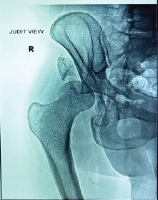

A 25-year-old male presented to the emergency department with a history of a fall from a motorcycle following a road traffic accident. Following initial resuscitation, plain radiographs of the knee were obtained, revealing a distal femur fracture (Fig. 1). Due to the complex nature of the injury and suspected intra-articular involvement, a computed tomography (CT) scan of the knee with 3D reconstruction was performed. It revealed isolated coronal fractures of both femoral condyles, confirming the diagnosis of a double Hoffa fracture (Fig. 2 and 3). Both the fracture fragments were separated, with no bony bridge connecting the two. The fracture was classified as AO 33-B3. After appropriate pre-operative planning and preparation, the patient was taken up for surgery.